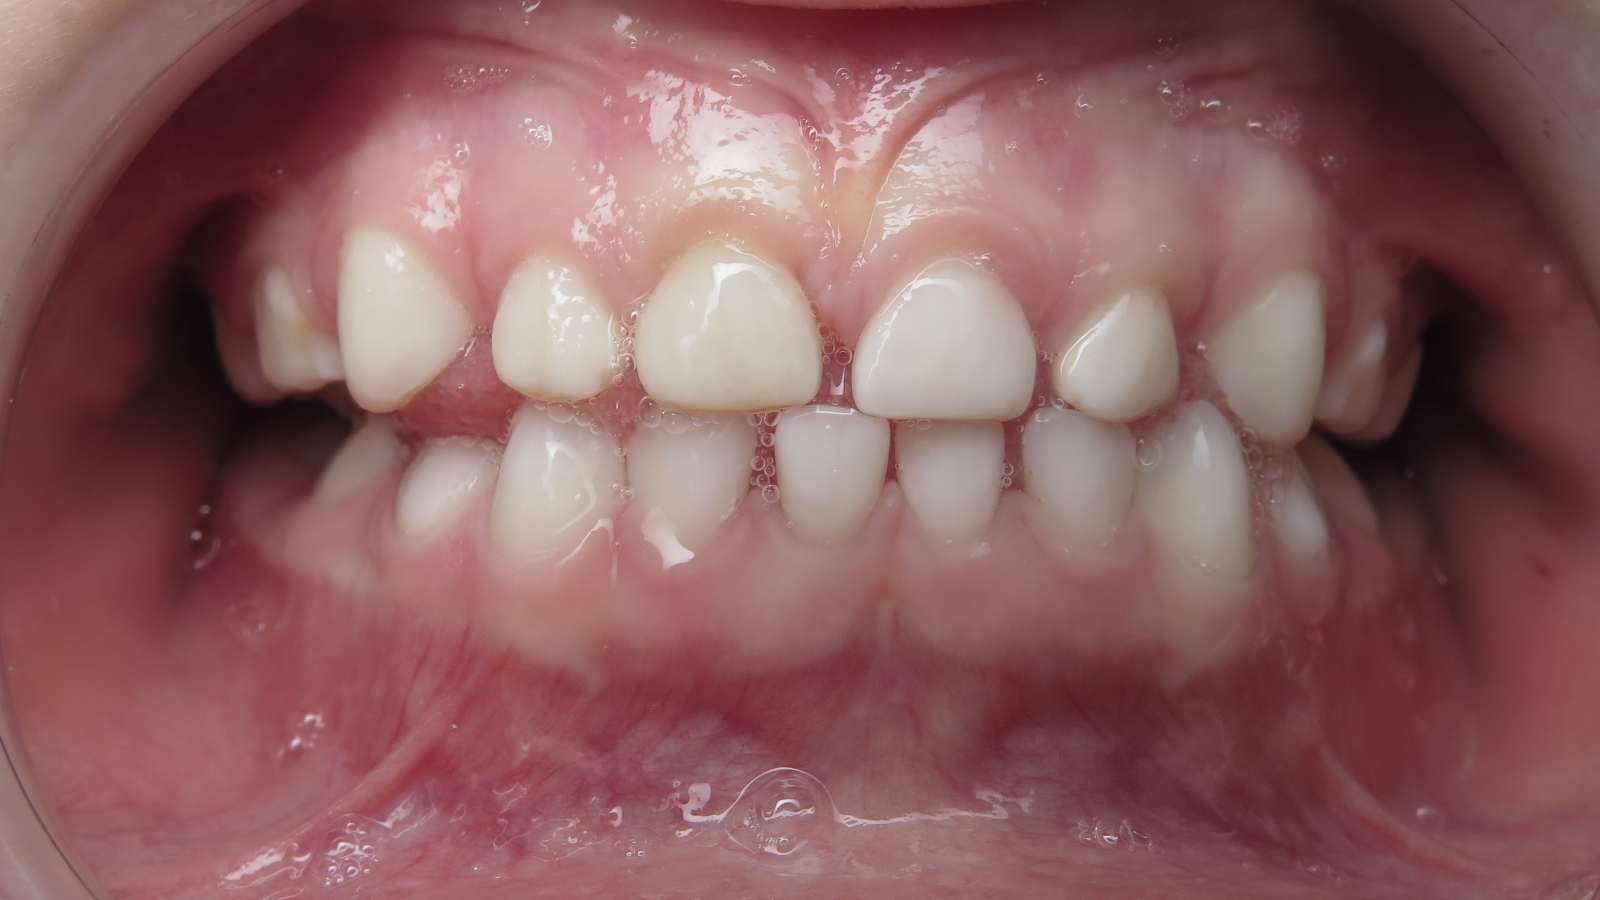

bilan début et en cours de traitement